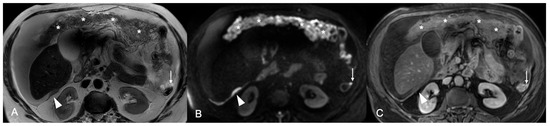

Figure 1